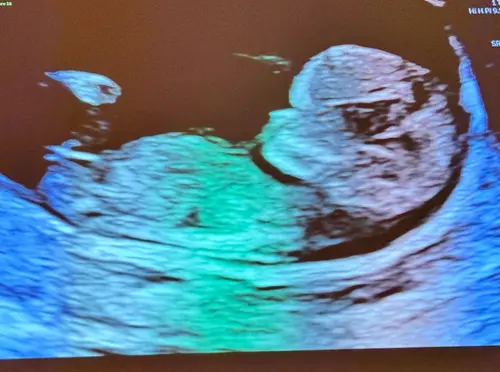

Hay! Dit is de 12 weken echo

Hoi allemaal! Is dit dan een meisje? Omdat het redelijk recht lijkt?

Nu nog een meisje, maar kan veranderen tot en met week 13